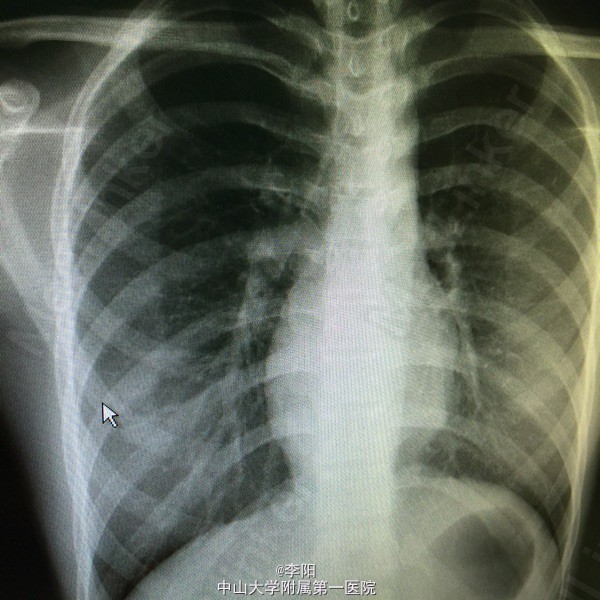

活动后心悸,气促十余年,体检发现心脏杂音一月。患者自幼身体发育不佳,体力较差,易患感冒,少量活动后即发作心悸,气促,休息后缓解,否认口唇青紫,蹲踞,无水肿,心衰史,患者一个月前体检时发现心脏杂音,心脏彩超提示:矫正性大动脉转位,三尖瓣重度关闭不全,左冠前降支及回旋支开口异位,永存左上腔,为期求进一步治疗入我院,起病以来,精神尚可,体力差,二便可,体重无明显变化。

三尖瓣听诊区可闻及收缩期杂音,未闻及心包摩擦音,超声提示矫正性大动脉转位,三尖瓣前瓣脱垂并中度关闭不全,冠状静脉窦扩张,形态右室功能正常。

矫正性大动脉转位,三尖瓣中度关闭不全,永存左上腔静脉,窦性心率,心功能三级。行大动脉转位矫治术,三尖瓣置换术